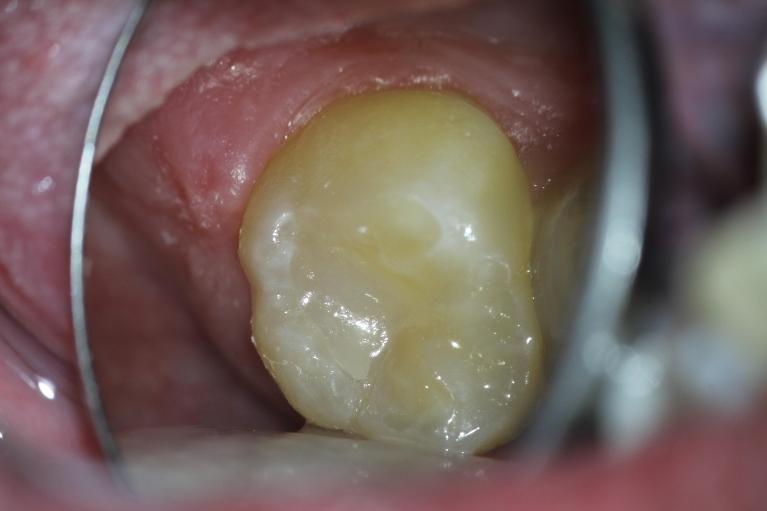

Welcome to our smile gallery, where you can browse photos of some of our best work. We hope that you find inspiration here for what is possible for your own smile. If you are considering cosmetic dentistry or you need help getting on track with your oral health, we look forward to hearing from you.

In the meantime, enjoy our before-and-after photos. We look forward to providing you with the same exceptional results.